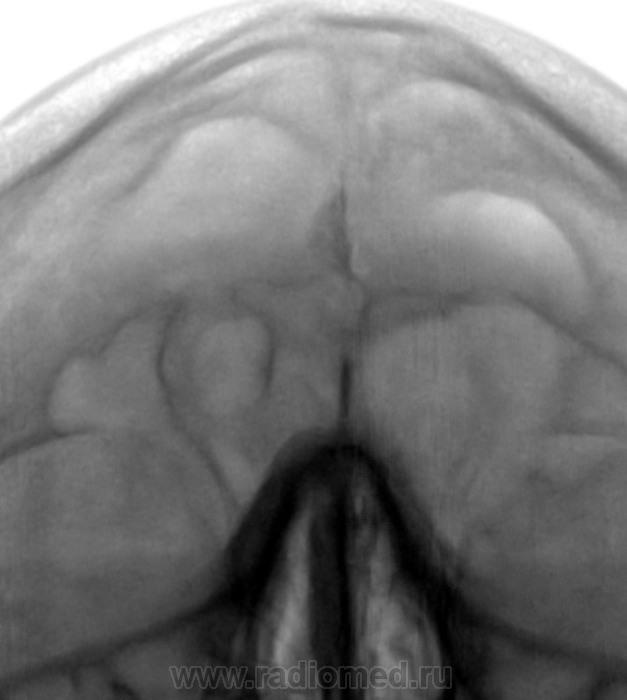

• https://radiomed.ru/sites/default/files/styles/case_slider_image/public/user/12/4.201403310002.jpg?itok=KgTRpkei

Пристеночные наслоения в лобных пазухах. В верхнечелюстной слева наверное больше на остеому похоже, хотя не исключил бы и кисту

А мне хочется норму написать.

Многокамерная пазуха ?

Так вопрос к локальному "окостенению" в районе фалькс церебри...